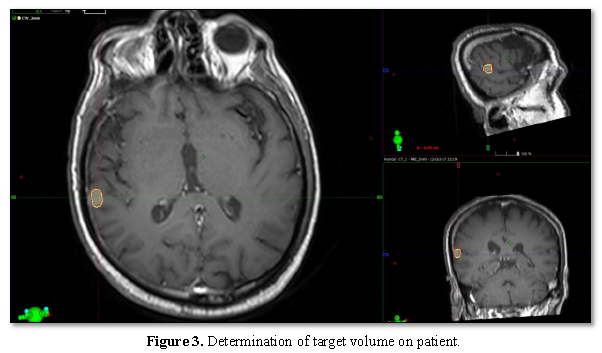

Determination of target volume

The target volumes were determined on the MR image by combining MRI and CT images by the radiation oncologist (Figure 3). Ten target volumes from four different patients were plotted on 2mm and 6mm fusion MR images separately. The data were analyzed by paired student t test. The target volumes obtained are shown in Table 1 and Table 2.